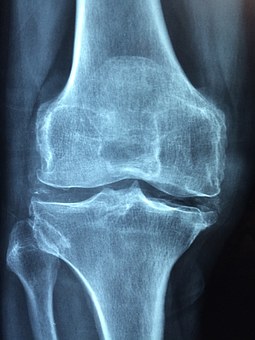

골다공증은 뼈의 강도가 약해져서 쉽게 골절되는 골격계 질환이다. 나이가 들면서 뼈 속의 칼슘이 밖으로 빠져나가게 되면서 노화가 주 원인이다. 여성의 경우 폐경 후 골 소실이 급속히 일어난다. 이는 여성 호르몬의 결핍 때문이다. 손목뼈, 척추, 고관절에서 골절이 자주 발생한다.